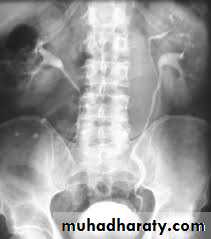

Anomalies of renal ascent and fusion:horseshoe kidney, pelvic kidney,malrotation

Abnormalities of renal ascent and fusion occur in weeks 6–9 of gestation, when the embryonic kidney is ascending to its definitive lumbar position (ascending as a result of rapid caudal growth of the embryo).Horseshoe kidney

This is the most common example of renal fusion. Prevalence is 1 in 400, with a male-to-female ratio 2:1. The kidneys lie vertically (instead of obliquely) and are joined at their lower poles (in 95%) by midline parenchymal tissue (the isthmus). The inferior mesenteric artery obstructs ascent of the isthmus. Consequently, the horseshoe kidney lies lower in the abdomen (at L3 or L4 vertebral level).

Normal rotation of the kidney is also prevented, thus the renal pelvis lies anteriorly, with the ureters also passing anteriorly over the kidneys and isthmus (but entering the bladder normally). Blood supply is variable, usually from one or more renal arteries or their branches, or from branches off the aorta or inferior mesenteric artery.

Most patients with horseshoe kidneys remain asymptomatic; however, infection and calculi may develop and cause symptoms.